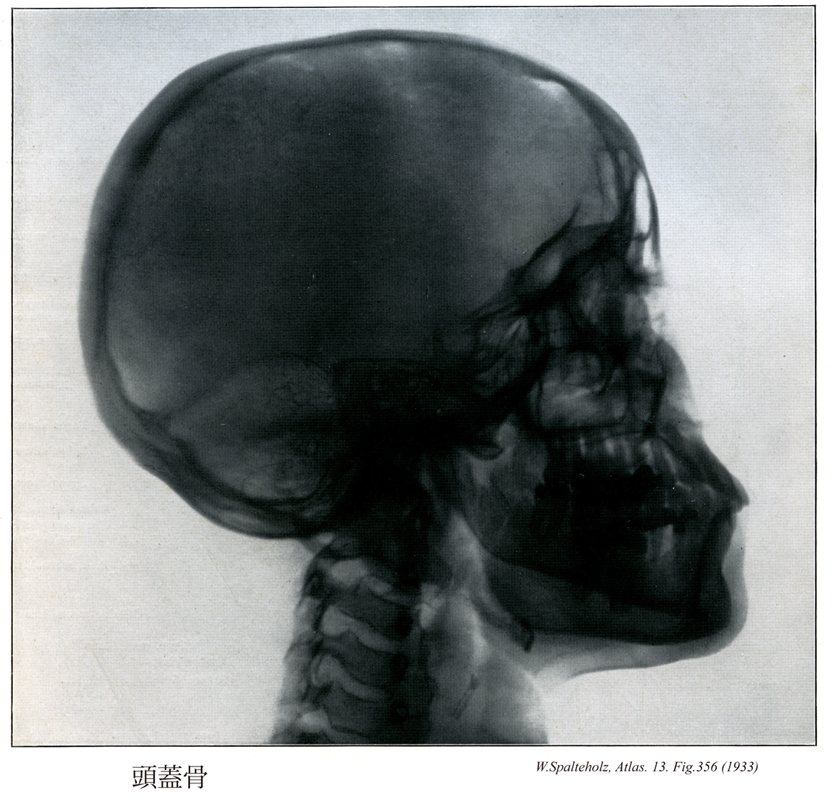

【Bones of cranium; Skull bones

頭蓋骨;ズガイコツ

Ossa cranii】

→(頭蓋は15種23個の骨、すなわち10種16個の頭蓋骨および5種7個の顔面骨とにより形成されている。頭蓋骨は中枢神経系および感覚器に接する部分を形成する骨格で後頭骨(1個)、蝶形骨(1個)、側頭骨(1対2個)、頭頂骨(1対2個)、前頭骨(1個)、篩骨(1個)、下鼻甲介(1対2個)、涙骨(1対2個)、鼻骨(1対2個)、及び鋤骨(1個)である。頭蓋を構成する骨の分類には諸学者による見解の相違があり、後頭骨、蝶形骨、側頭骨、頭頂骨、前頭骨の5種7個を脳頭蓋とし、他の10種16個を顔面骨とする意見もある。)